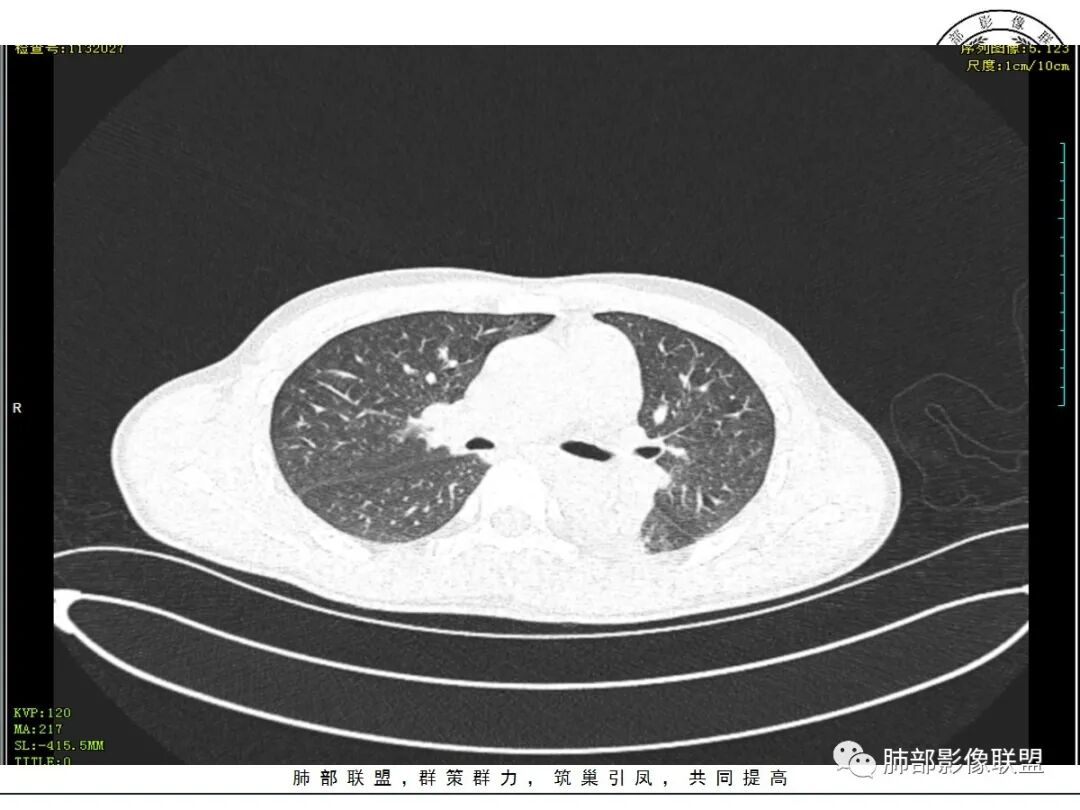

双肺上叶,下叶背段多发斑片状实变影,以胸膜下分布为主,部分重力作用,以背侧为主,部分小叶间质增厚,部分周围伴有散在磨玻璃影,边界欠清,临床急性病程,血象增及PCT明显增高,意识模糊,考虑:吸入性肺炎?鉴别:AHP?CEP?PCP

37岁男性 气促 两肺对称分布磨玻璃及小叶间隔增厚,两肺上叶后段及下叶背段为著,有重力分布,下部密度较高,请结合病史排查肺水肿,理化性肺泡损伤

双肺叶透亮度对称性减低,呈磨砂状,小叶间隔规则增厚,上叶为甚,左右肺叶中轴间质增厚(示淋巴回流障碍),双肺叶弥散磨GGO征,以肺腺泡分布,双肺上,下叶融合片状,有重力分布特点,心脏大,肺动脉干增粗,首选心源性肺水肿,但无胸腔积液。与急性肺损伤和ARDS鉴别

双肺弥漫性病变以上肺,向心性,背部分布为主,肺动脉干无增粗,急性起病,典型的吸入性肺炎。

既有重力分布特点,也有吸入性特点,这个病例缺乏了特殊病史,是喝醉后还是别的原因引起的误吸。

青年男性,气促7小时入院,意识模糊,白细胞及中性粒明显增高,PCT增高,CRP不高,心率快,体温正常,血压正常。胸部CT:双肺上叶小叶间隔光滑增厚,中轴间质增厚,弥漫性磨玻璃、多发斑片影,以上肺、背侧分布为主。影像表现考虑为肺水肿。病因:病史不支持肾功能衰竭、心源性、高原性肺水肿,无发热,似乎也不支持细菌、病毒、真菌等感染引起。吸入毒物?吸入水?

病灶的分布以上肺为主

确实要考虑吸入,倾向于吸入的是气体类的可能,因为朝上走

结合病史,最终诊断是 “急性烟雾吸入性肺损伤”,影像学表现主要是肺水肿及弥漫性肺泡损伤改变,因为烟雾气体吸入肺内分布以上肺显著,因此影像学表现也是累及上肺更明显。损伤因素包括大量一氧化碳 二氧化碳 一氧化氮等燃烧产生的有毒气体,也有烟雾粉尘颗粒对气道黏膜的损伤。